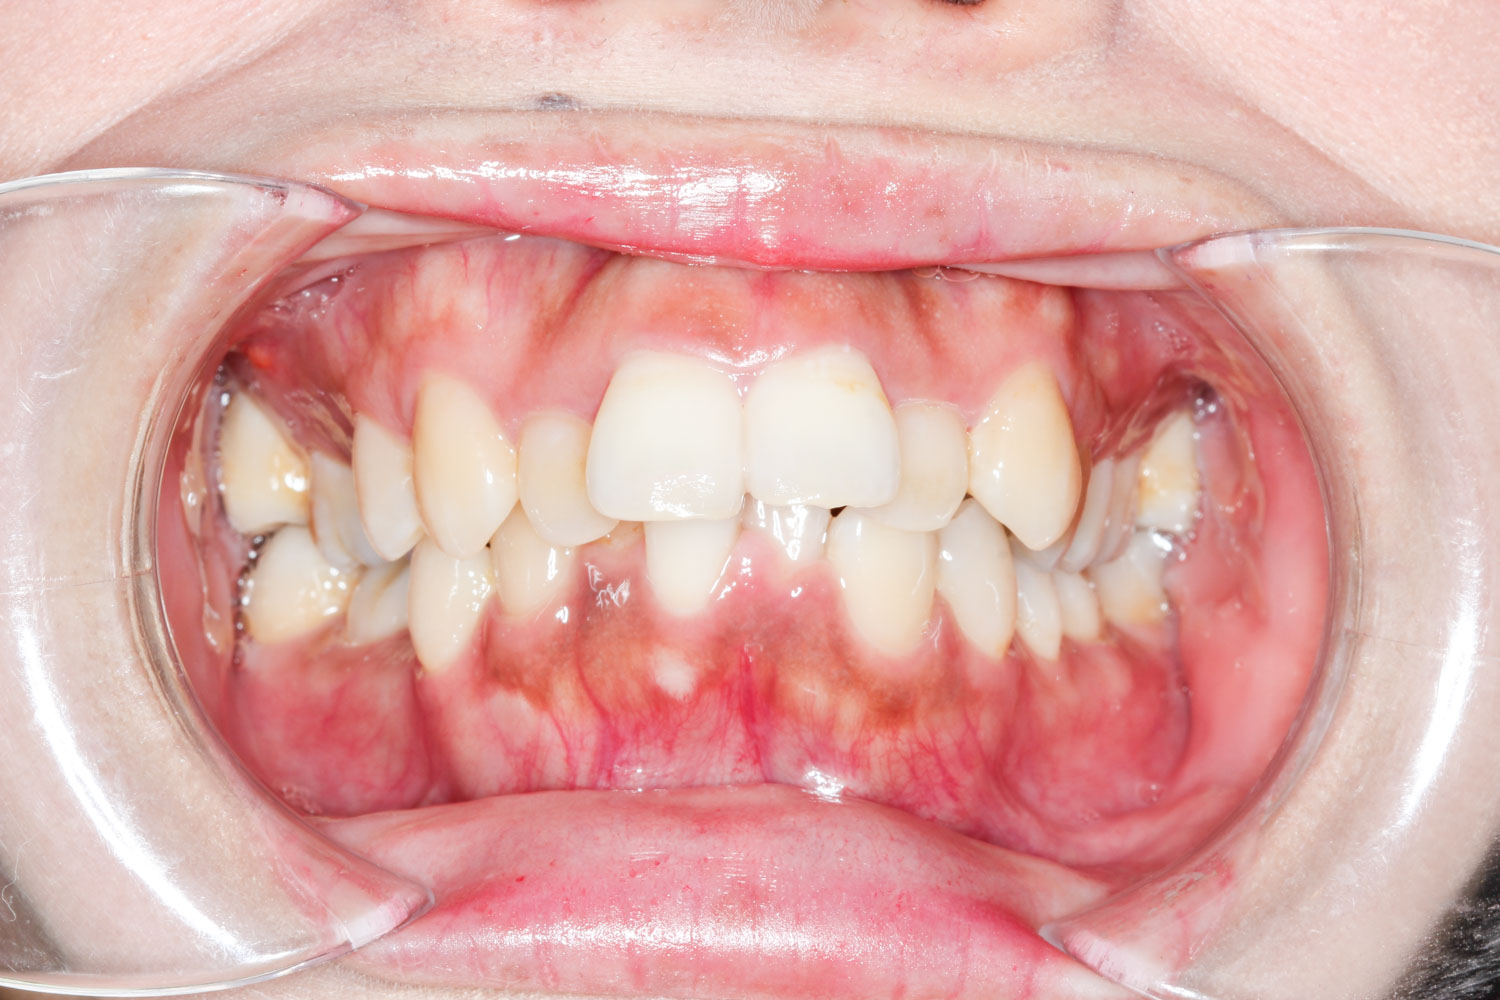

Before

年齢 10代

治療装置 表側の矯正装置(ホワイトコース)

治療内容 上下左右4本抜歯

治療期間 2年1か月

リスク 歯の移動に伴う痛み、歯肉退縮、歯根吸収、歯肉炎、虫歯

主訴 ガタガタが気になる

症状 叢生(ガタガタ)

治療回数 25回程度

総額費用 105万円程度